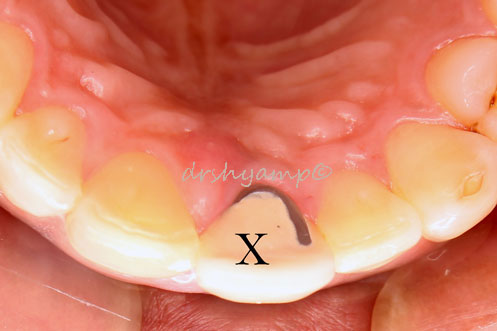

Cyst Enucleation